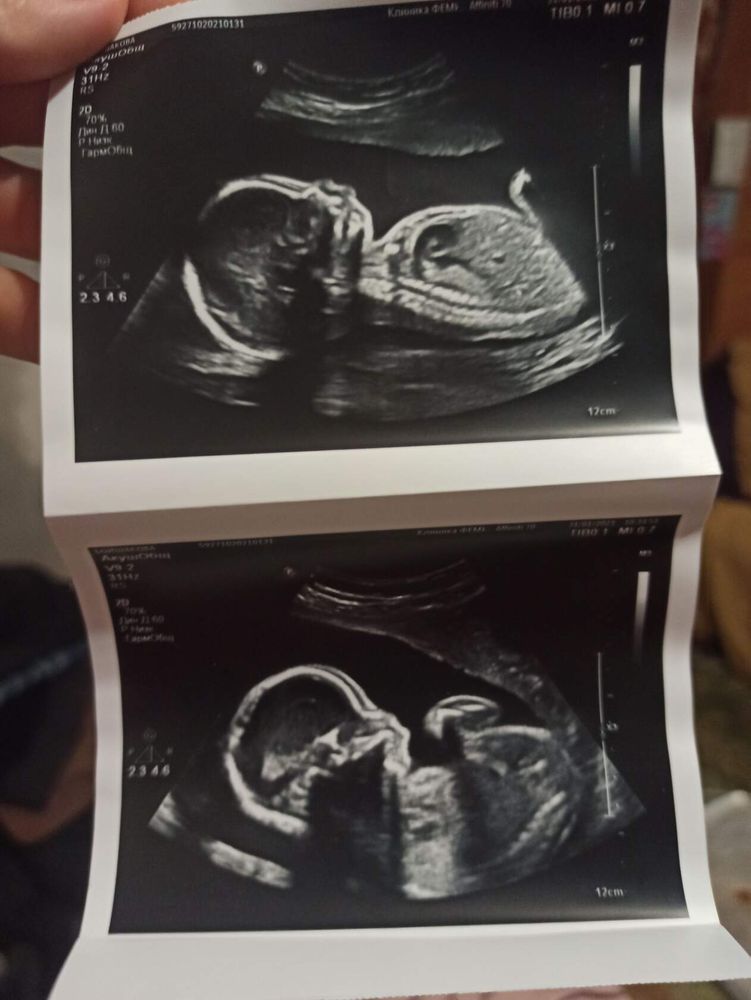

Я вижу голову и живот)) как по ним определить пол я хз🤣

Профиль ребёнка

Тут не видно и рано

Изображение Это мой сынок😁

Малинка, тут спрятано причинное место )

Девчуля

елена, проверим в 16 недель ) на снимке тоже кажется что девочка , а по видео 100% мальчтк ))) не знаю где плоскость изображения верная , вроде везде одинаково лежит

У вас девочка.

Профитроль, проверим в 16 недель ) по видео я увидела только мужскую пипку кверху задранную . Интересно какой срез был более достоверный ))

Девочка)

Тут нет этого участка))) как сказала узист ждите второго скрининга 😄 слава богу, я сдала кровь на определение 🙌

Саша, мы пойдём в 16-17 недель смотреть пол )

Саша, ой пипку видно ага )) но на видео мне тоже показалось что пипка мужская мелькает )))